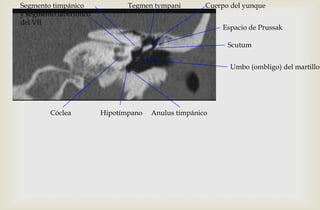

Umbo (ombligo) del martillo

Scutum

Espacio de Prussak

Tegmen tympani

Hipotímpano Anulus timpánicoCóclea

Segmento timpánico

y segmento laberíntico

del VII